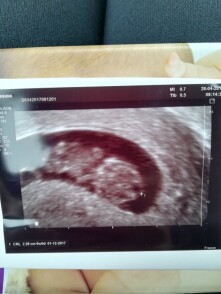

Dobrý den, dnes jsem začala lehce špinit, poté ze mě vyšla nějaká “sraženina” (přikládám fotku), poté se rozběhlo silné krvácení a bolesti břicha, může se jednat o potrat? Děkuji.

Dobrý den, skutečně se může jednat o potrat. Potvrzení či vyvrácení této hypotézy může pouze ultrazvukové vyšetření. Zajděte ke svému obvodnímu gynekologovi, jelikož je důležité zkontrolovat, zda dutina děložní je čistá, jelikož potrat nemusí být kompletní. V tomto případě se preferuje farmakologická metoda řešení (tzn. konzervativní), další možností je pak revize dutiny děložní pod celkovou narkózou. Hezký den